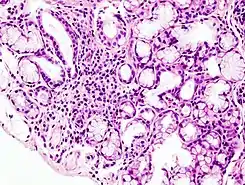

![]() Imagen histopatológica de infiltración en la glándula salivar menor asociada con el síndrome de Sjögren. Biopsia labial. H & E stain. | ||